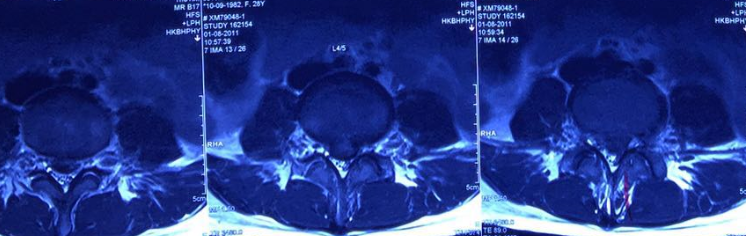

Illustrated MR 1, MR2

Severe lumbar disc herniation in the fourth and fifth segments in August 2011.